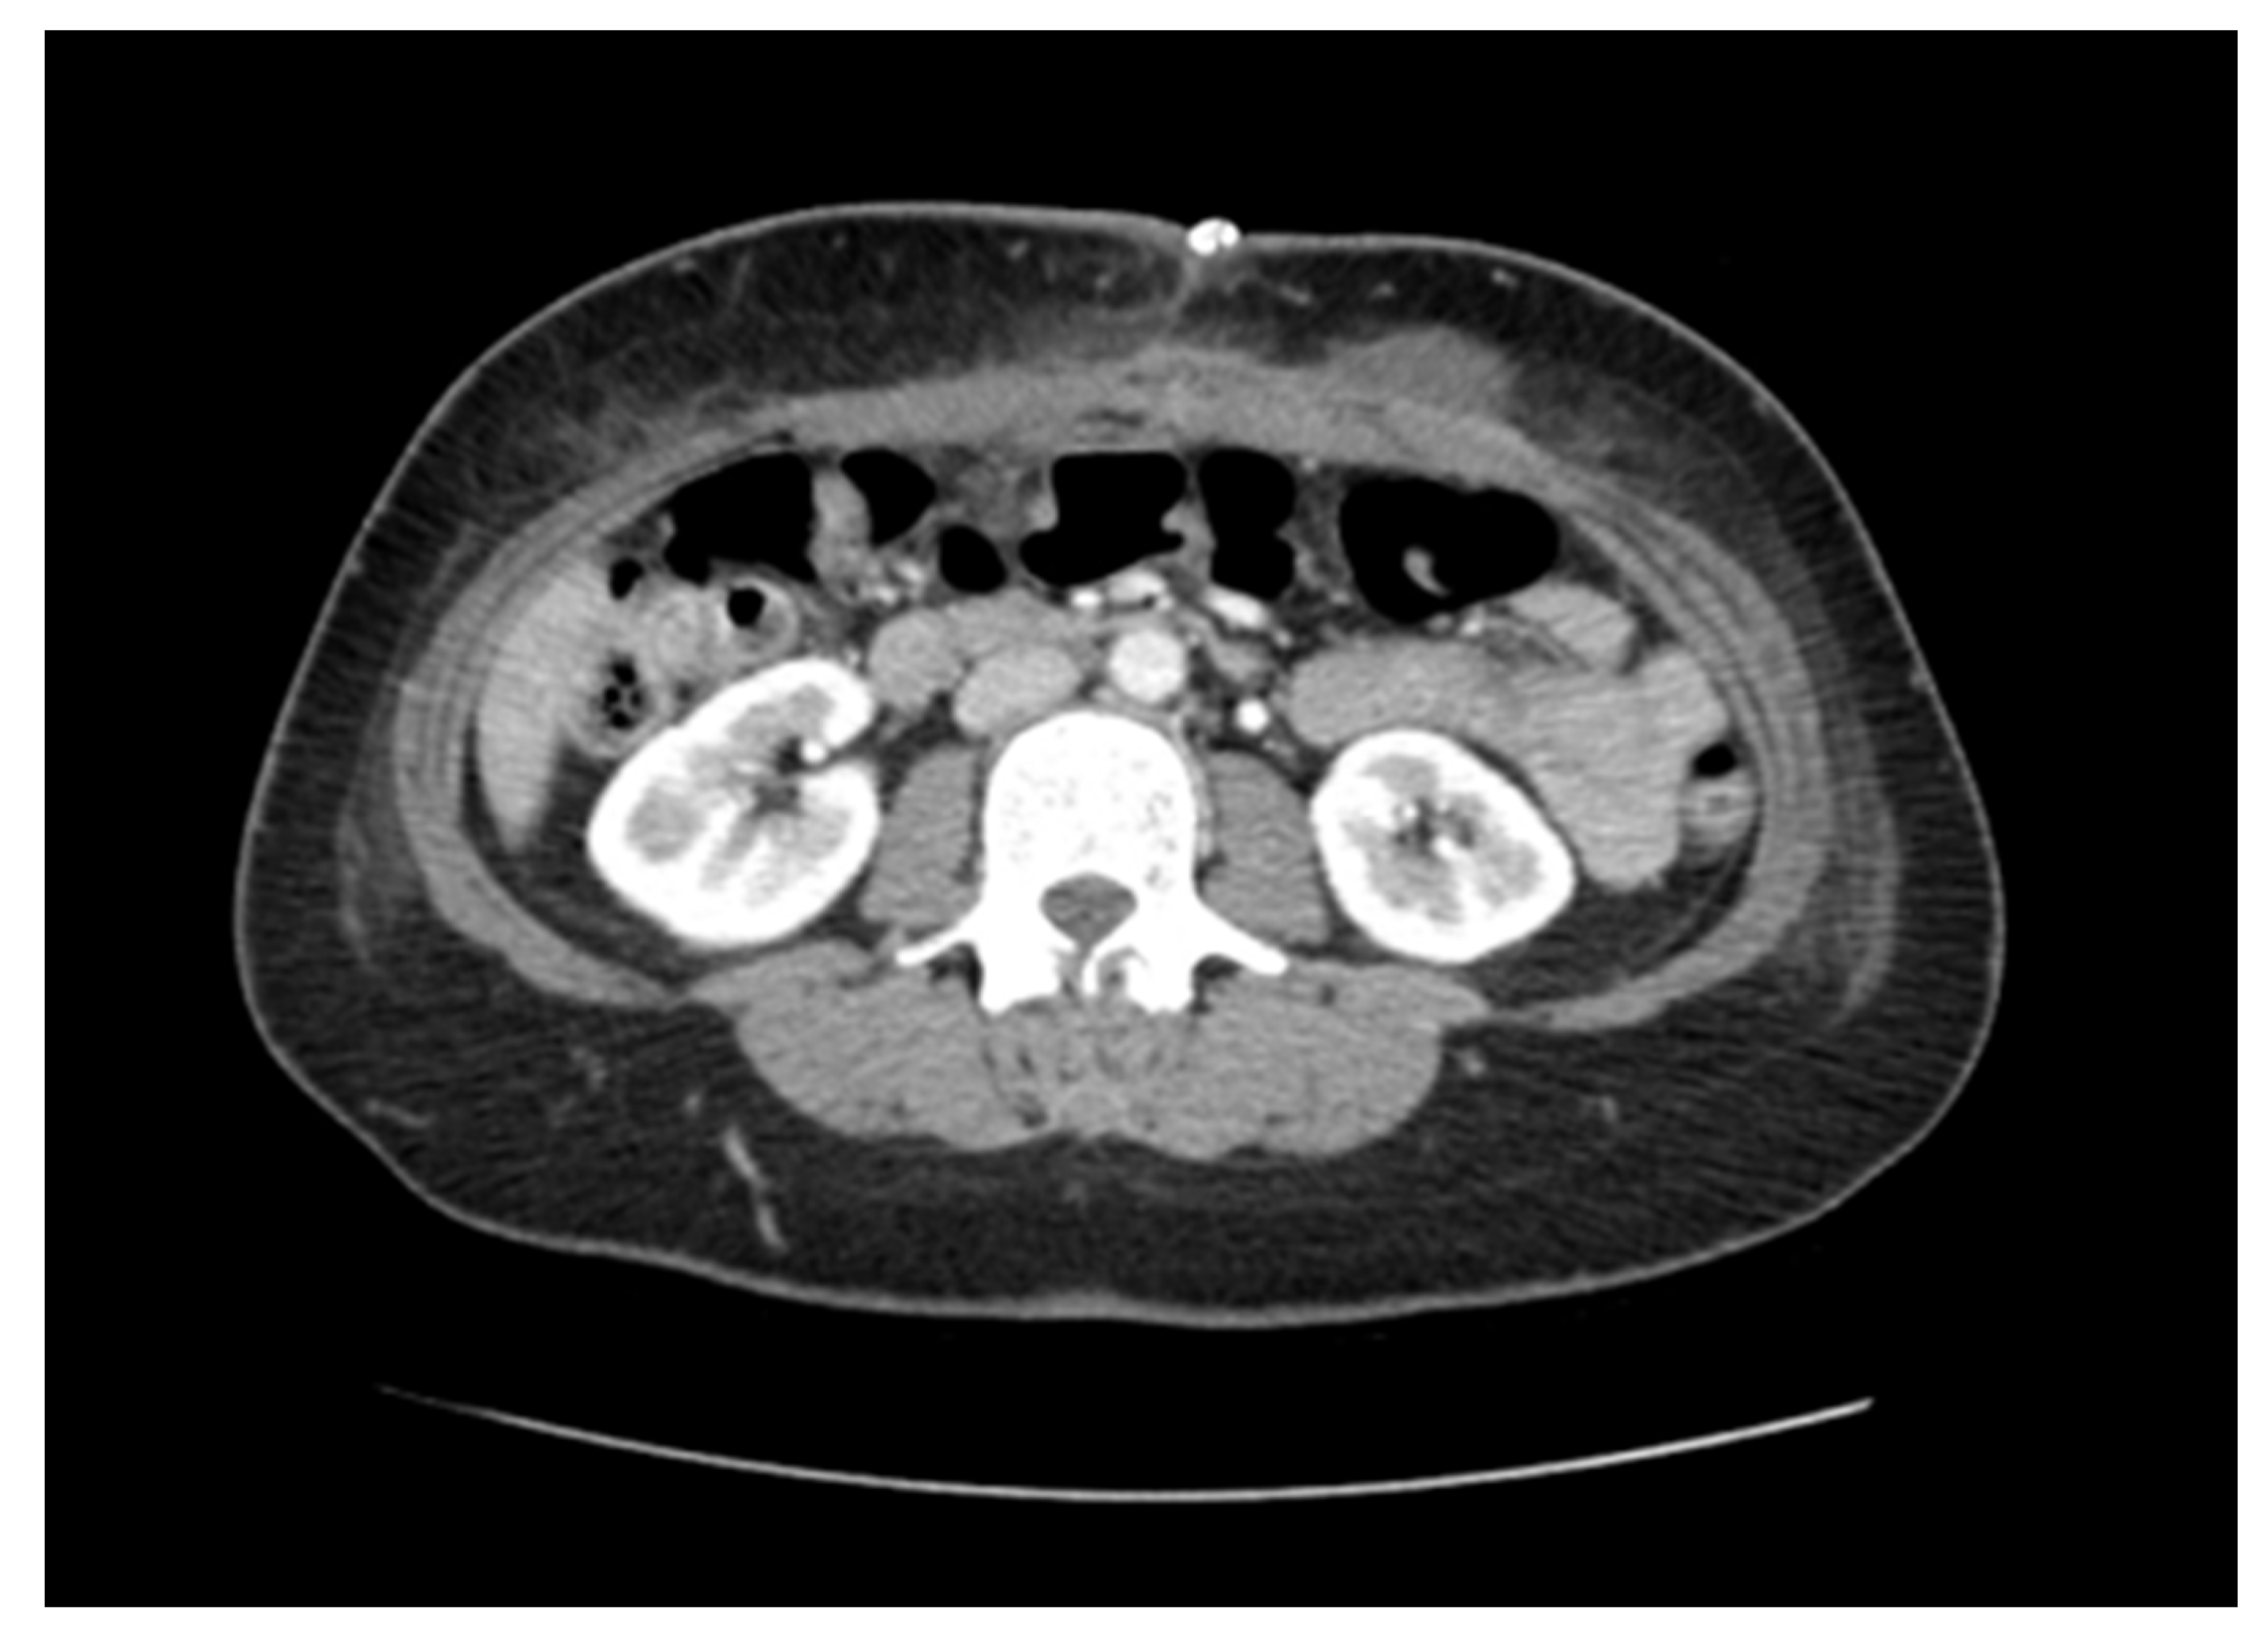

The abdominal wall is a multilayered structure that wraps around and protects the abdominal viscera. Web hen repairing larger hernias it can sometimes be difficult to bring the edges of the abdominal wall back together. Web Abdominal wall reconstruction is a surgical procedure used to restore the structural and functional integrity of the abdominal muscles.